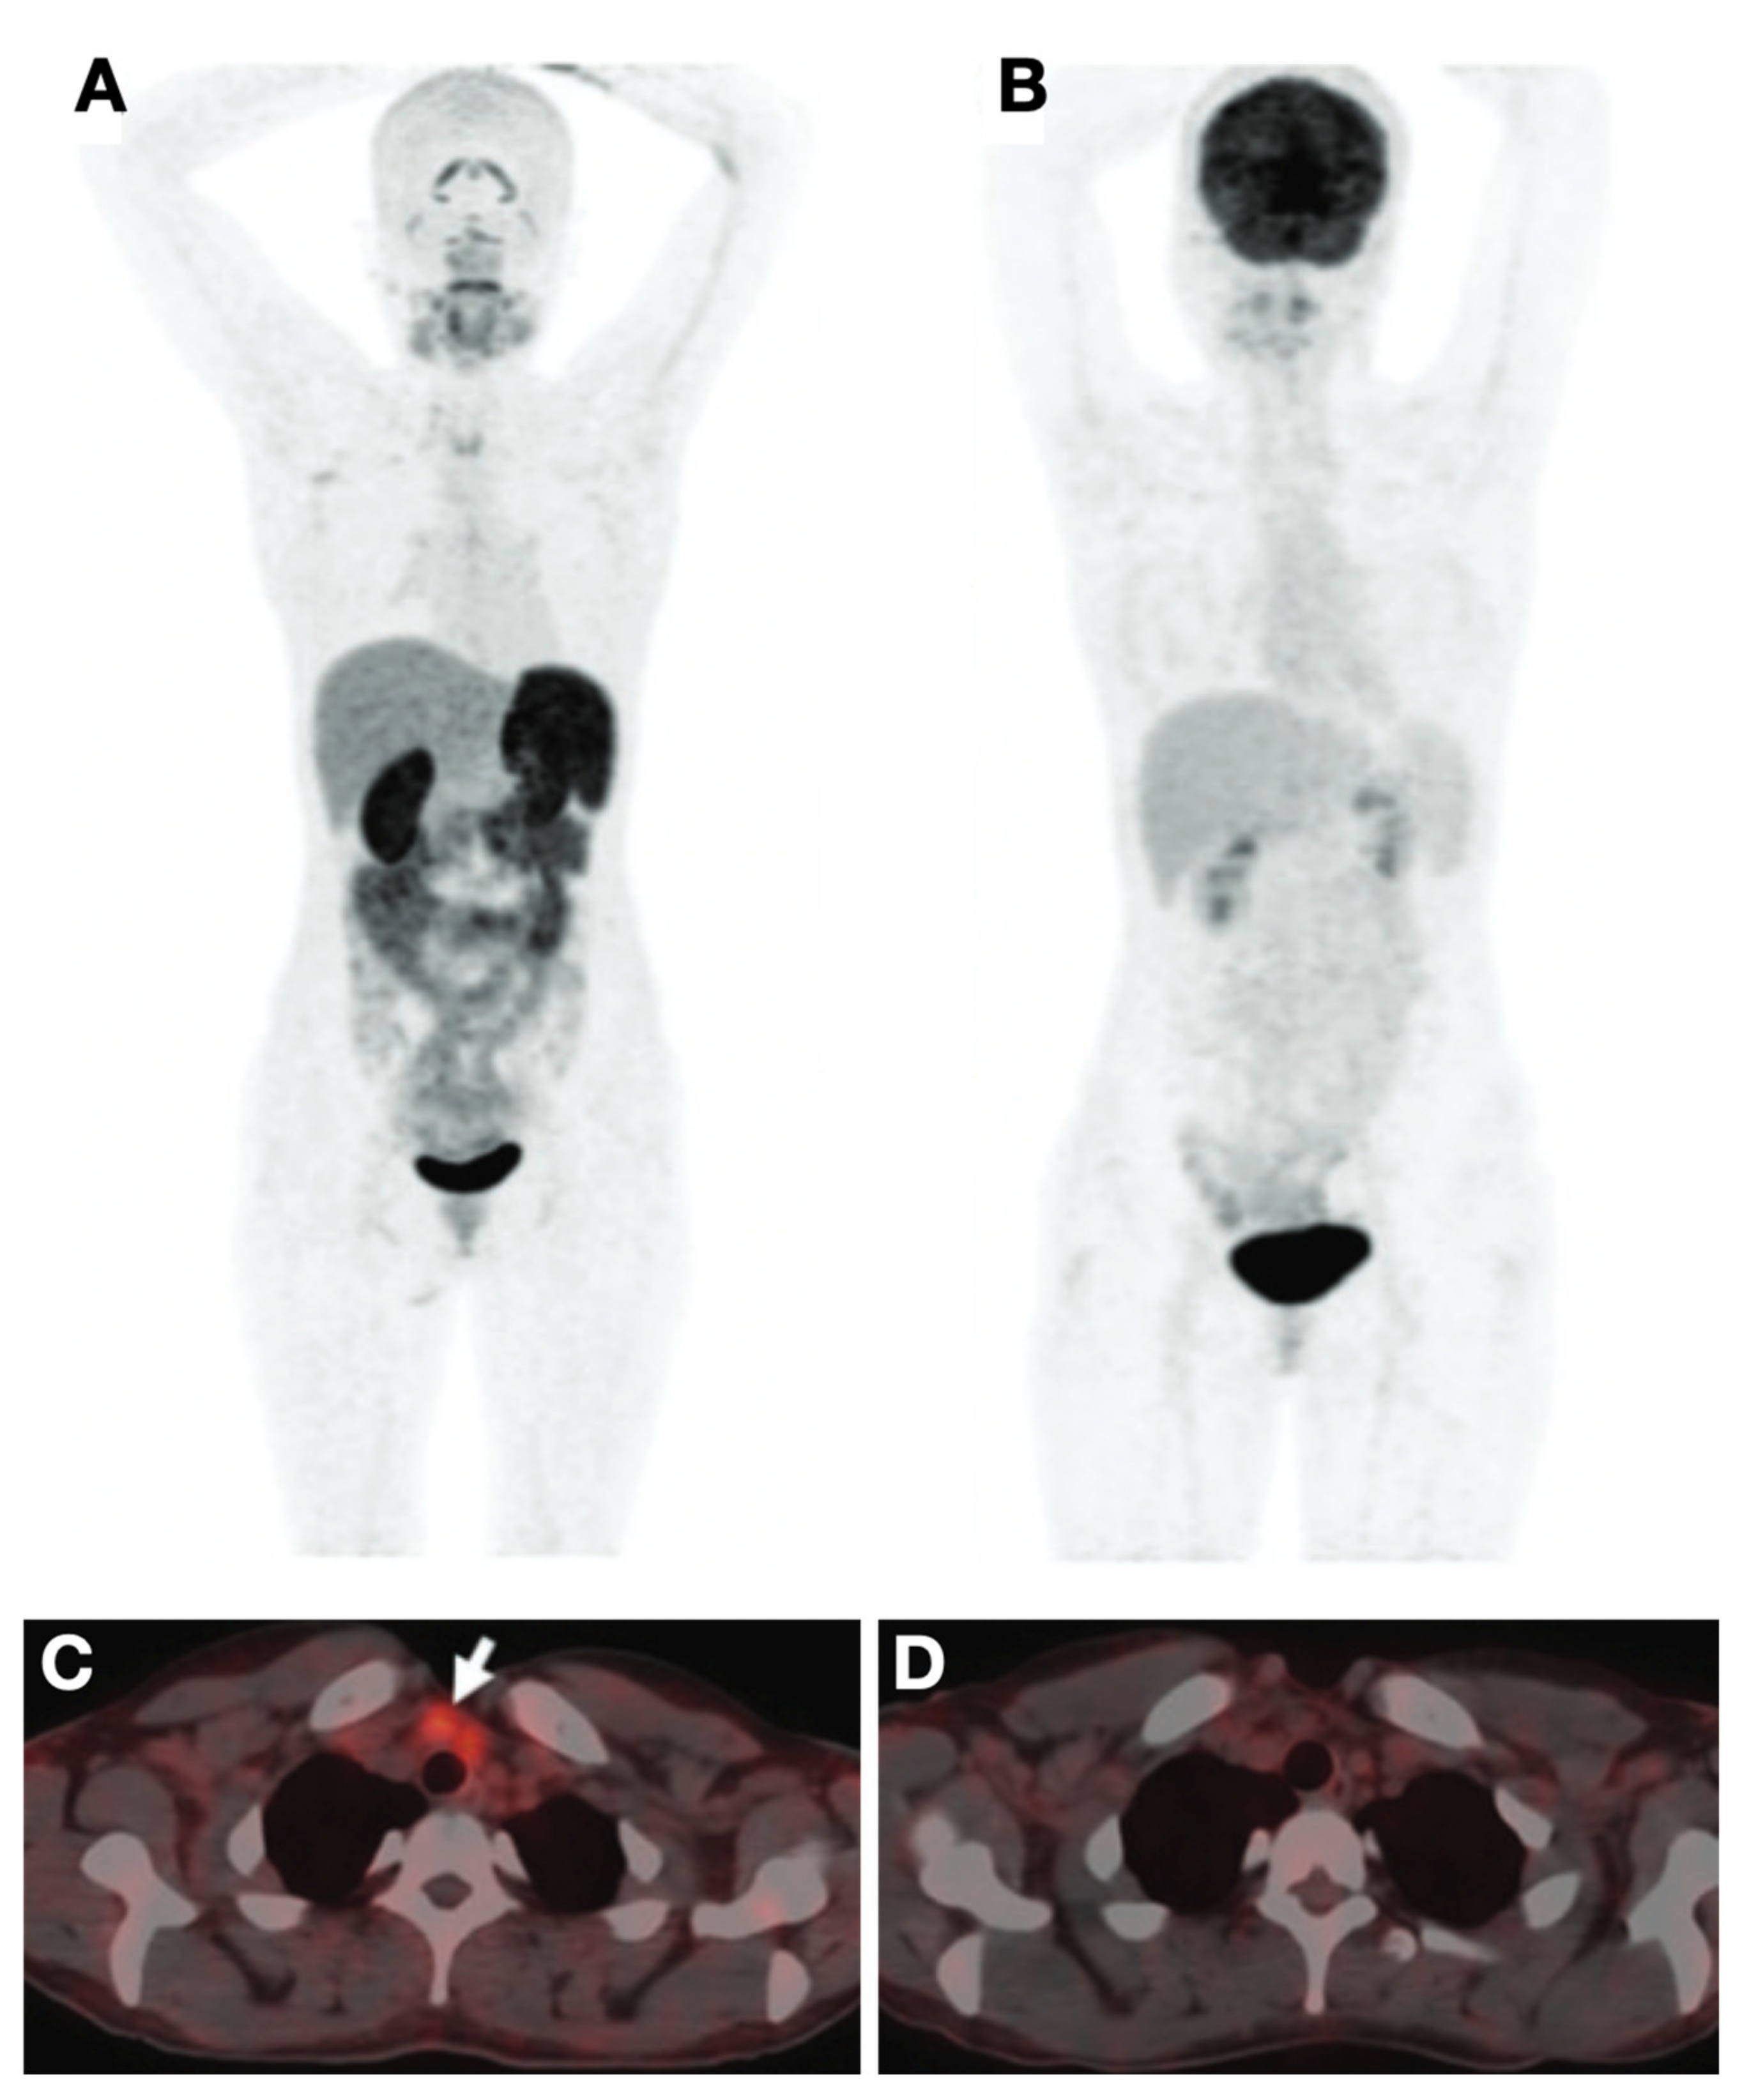

- Ho, A.L.; Grewal, R.K.; Leboeuf, R.; Sherman, E.J.; Pfister, D.G.; Deandreis, D.; Pentlow, K.S.; Zanzonico, P.B.; Haque, S.; Gavane, S.; et al. Selumetinib-Enhanced Radioiodine Uptake in Advanced Thyroid Cancer. N. Engl. J. Med. 2013, 368, 623–632. [Google Scholar] [CrossRef] [Green Version]

- Dunn, L.A.; Sherman, E.J.; Baxi, S.S.; Tchekmedyian, V.; Grewal, R.K.; Larson, S.M.; Pentlow, K.S.; Haque, S.; Tuttle, R.M.; Sabra, M.M.; et al. Vemurafenib Redifferentiation of BRAF Mutant, RAI-Refractory Thyroid Cancers. J. Clin. Endocrinol. Metab. 2018, 104, 1417–1428. [Google Scholar] [CrossRef]